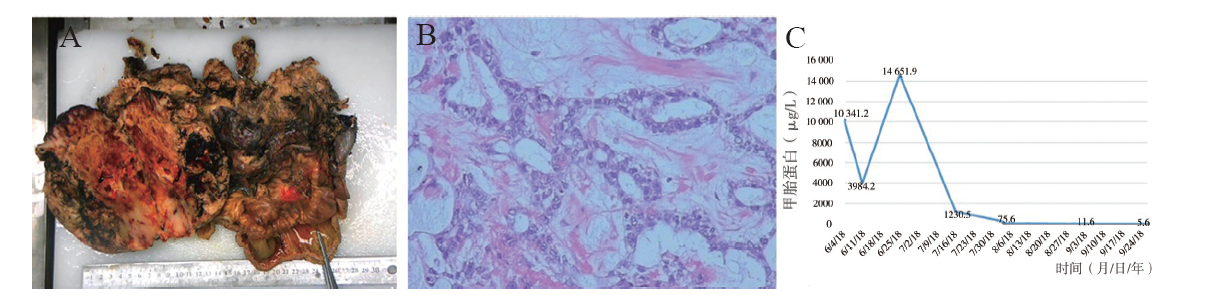

初步诊断:卵巢卵黄囊瘤可能。2018年6月6日行剖腹探查,术中见盆腔巨大包块(图2A)与乙状结肠、直肠、子宫后壁及右侧卵巢粘连,分离粘连后见子宫双侧附件外观正常,子宫直肠陷凹封闭,包块来源于后腹膜,予经腹盆腔巨大肿物切除术、小肠部分切除术、盆腔粘连松解术。术后病理结果提示镜下见异形细胞呈腺样、条索状或迷路样排列,可见Schiller-Duval(S-D)小体,腺样结构内的被覆上皮部分肥胖,部分扁平,核分裂易见,间质疏松、黏液样变性明显,并见嗜酸性小体。免疫组织化学染色:角蛋白(CK,+),胎盘碱性磷酸酶(PLAP,+),甲胎蛋白(+),HCG(-),CD30(-),Oct3/4(-),上皮膜抗原(EMA,-),抑制素(inhibin,-),波形蛋白(Vim,-),细胞增殖抗原Ki67(40%+),Gly-3(部分+),见图2B。考虑卵黄囊瘤。术后予依托泊苷150 mg、卡铂900 mg、博来霉素15 mg(BEP方案)静脉化学治疗,共化学治疗6次。第3次化学治疗后(2018年8月6日)复查甲胎蛋白降至正常(图2C),彩超未见明显异常肿物。随访1年至撰稿日未见肿瘤复发。

图2 一例后腹膜卵黄囊瘤患者的术中切除肿物、病理结果以及手术前后血清甲胎蛋白水平

A:术中切除后腹膜肿物大体标本;B:后腹膜肿物HE染色(×400);C:患者术前及术后血清甲胎蛋白水平变化

血清甲胎蛋白升高是卵黄囊瘤的标志,有助于卵黄囊瘤的诊断。血清甲胎蛋白的连续测定对监测疾病发展和治疗反应有重要意义[1]。Talerman等最早于1980年提出血清甲胎蛋白升高可用于诊断卵黄囊瘤,同时可用于评估肿瘤恶性程度及复发。本例患者经手术及BEP方案化学治疗后,血清甲胎蛋白由10 341.2 μg/L降至正常,因而血清甲胎蛋白可作为后腹膜卵黄囊瘤的重要肿瘤标志物,并用于长期监测肿瘤复发及远处转移。术前影像学检查有助于标记卵黄囊瘤位置,但卵黄囊瘤缺乏特征性影像学表现。CT平扫可呈等密度或低密度,部分实性成分增强。MRI平扫可见囊性部分呈明显的长T1、T2信号,实性部分T1以等信号和低信号为主,T2呈高信号[5,6]。本例患者术前盆腔MRI提示卵巢来源恶性肿瘤,由于缺乏特征性影像学表现,与术中发现为后腹膜来源肿瘤不相符。病理学检查是诊断的金标准。卵黄囊瘤的常见的组织形态学构象包括特异性S-D小体微囊性结构、腺泡-腺管样结构、多囊状结构、黏液瘤样结构、实性团巢状结构、肝样型卵黄囊瘤、原始腺管样结构等,肿瘤细胞形态多样,异型性明显,核分裂像多见[7]